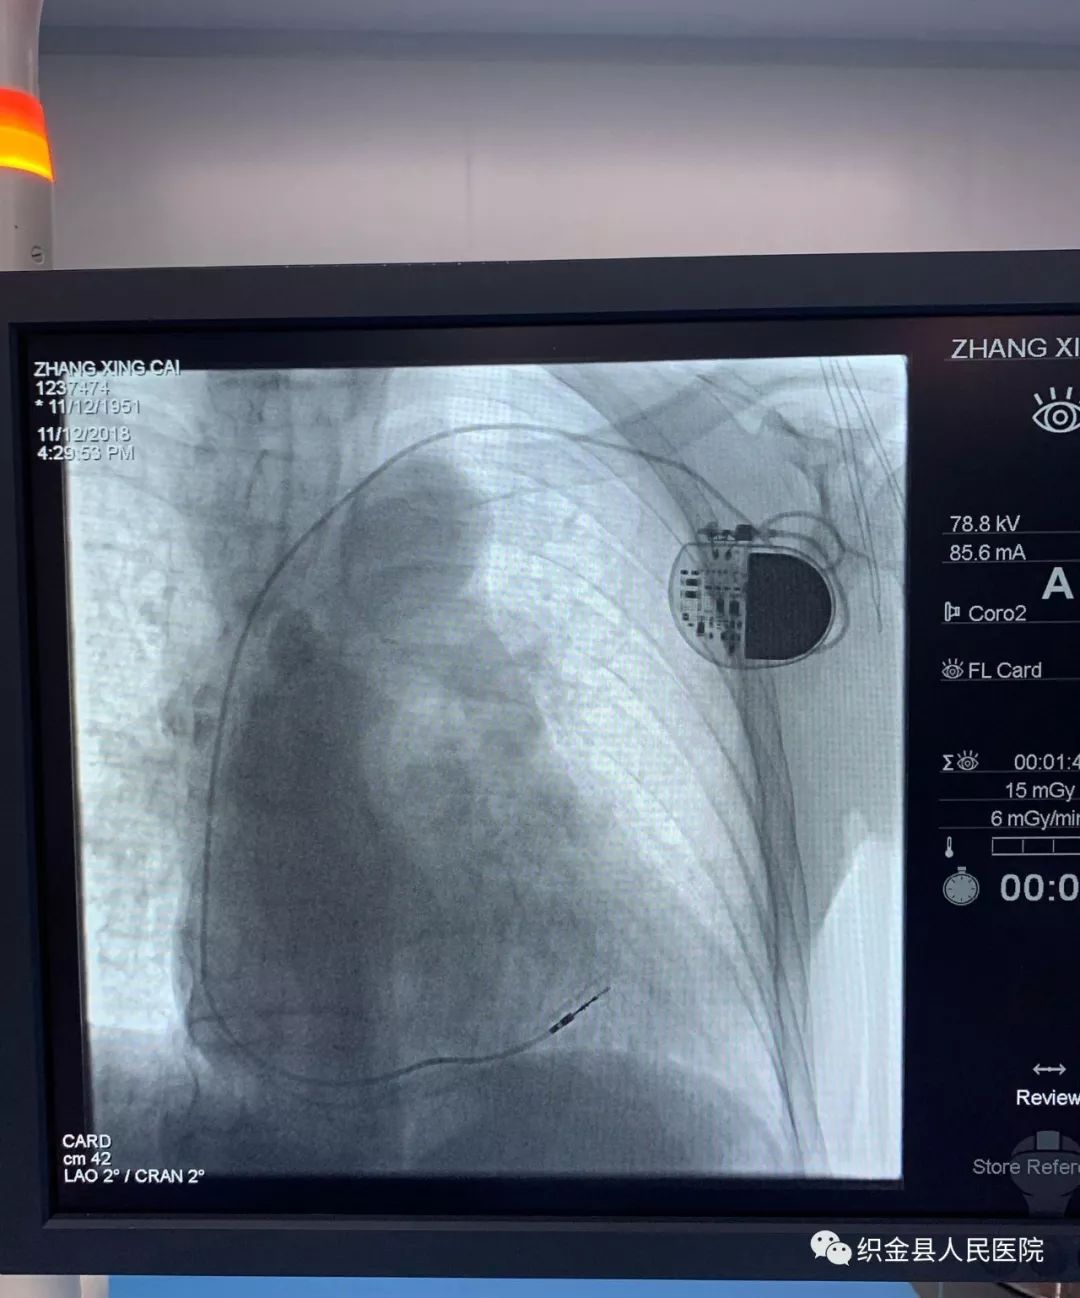

68岁的张先生有反复胸闷气促3年的病史,病程偶有头昏、黑矇的症状,心电图提示房颤心律,三度房室传导阻滞,冠脉造影检查提示冠状动脉粥样硬化,排除冠心病,患者心率较慢,最慢时22次/分,随时有发生猝死的风险,有起搏器植入适应症。 为保证患者安全、手术顺利进行,术前特邀请贵州省人民医院、贵州省心血管病医院心内科主任医师俞杉进行手术指导、术前讨论,认真分析患者的病情,并就手术细节等相关事项进行了仔细分析和研究,制定详细周密的手术方案。

11月12日16时38分,由心内科主任王中山带领的手术团队,在贵州省人民医院、贵州省心血管病医院心内科主任医师俞杉指导下,医护团队默契配合、细致操作,我院首例永久性心脏起搏器植入术顺利完成,以60次/分的频率起搏,术后患者无胸闷、气促,无头昏、黑矇的症状,恢复很好。